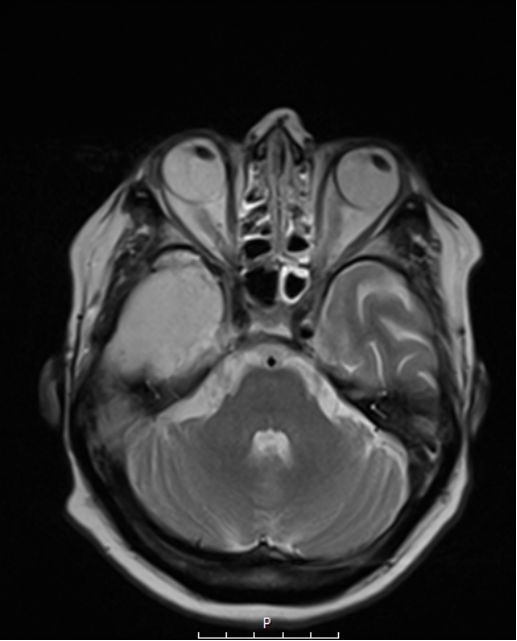

Ο συνδυασμός λοιπόν ενός ασφαλούς χειρουργείου με ταυτόχρονη ολική αφαίρεση του όγκου αποτελεί τον στόχο της σύγχρονης χειρουργικής νευρο-ογκολογίας. Μια υπερολική εξαίρεση στα πλαίσια μιας κροταφικής λοβεκτομής απεικονίζεται στις εικόνες 1 και 2. Αυτό είναι σαφέστατα πιο πιθανό να προσφερθεί από ειδήμονες νευροχειρουργούς (Gousias K, 2024) με ειδική εκπαίδευση σε μεγάλα κέντρα, μεγάλη χειρουργική εμπειρία και εξειδίκευση στην χειρουργική των όγκων καθώς και διεθνή αναγνώριση τους.